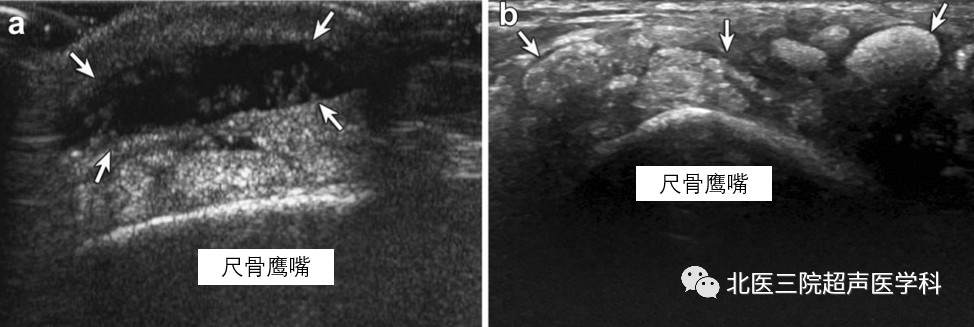

尺骨鹰嘴滑囊:2位不同的患者。左图病例2--66岁男性,外伤所致尺骨鹰嘴滑囊炎。超声显示尺骨鹰嘴滑囊内液体增多,伴滑膜增生(白色箭);右图病例3--63岁男性,痛风性尺骨鹰嘴滑囊炎,扩张的滑囊内可见多发团状高回声痛风石(白色箭)。